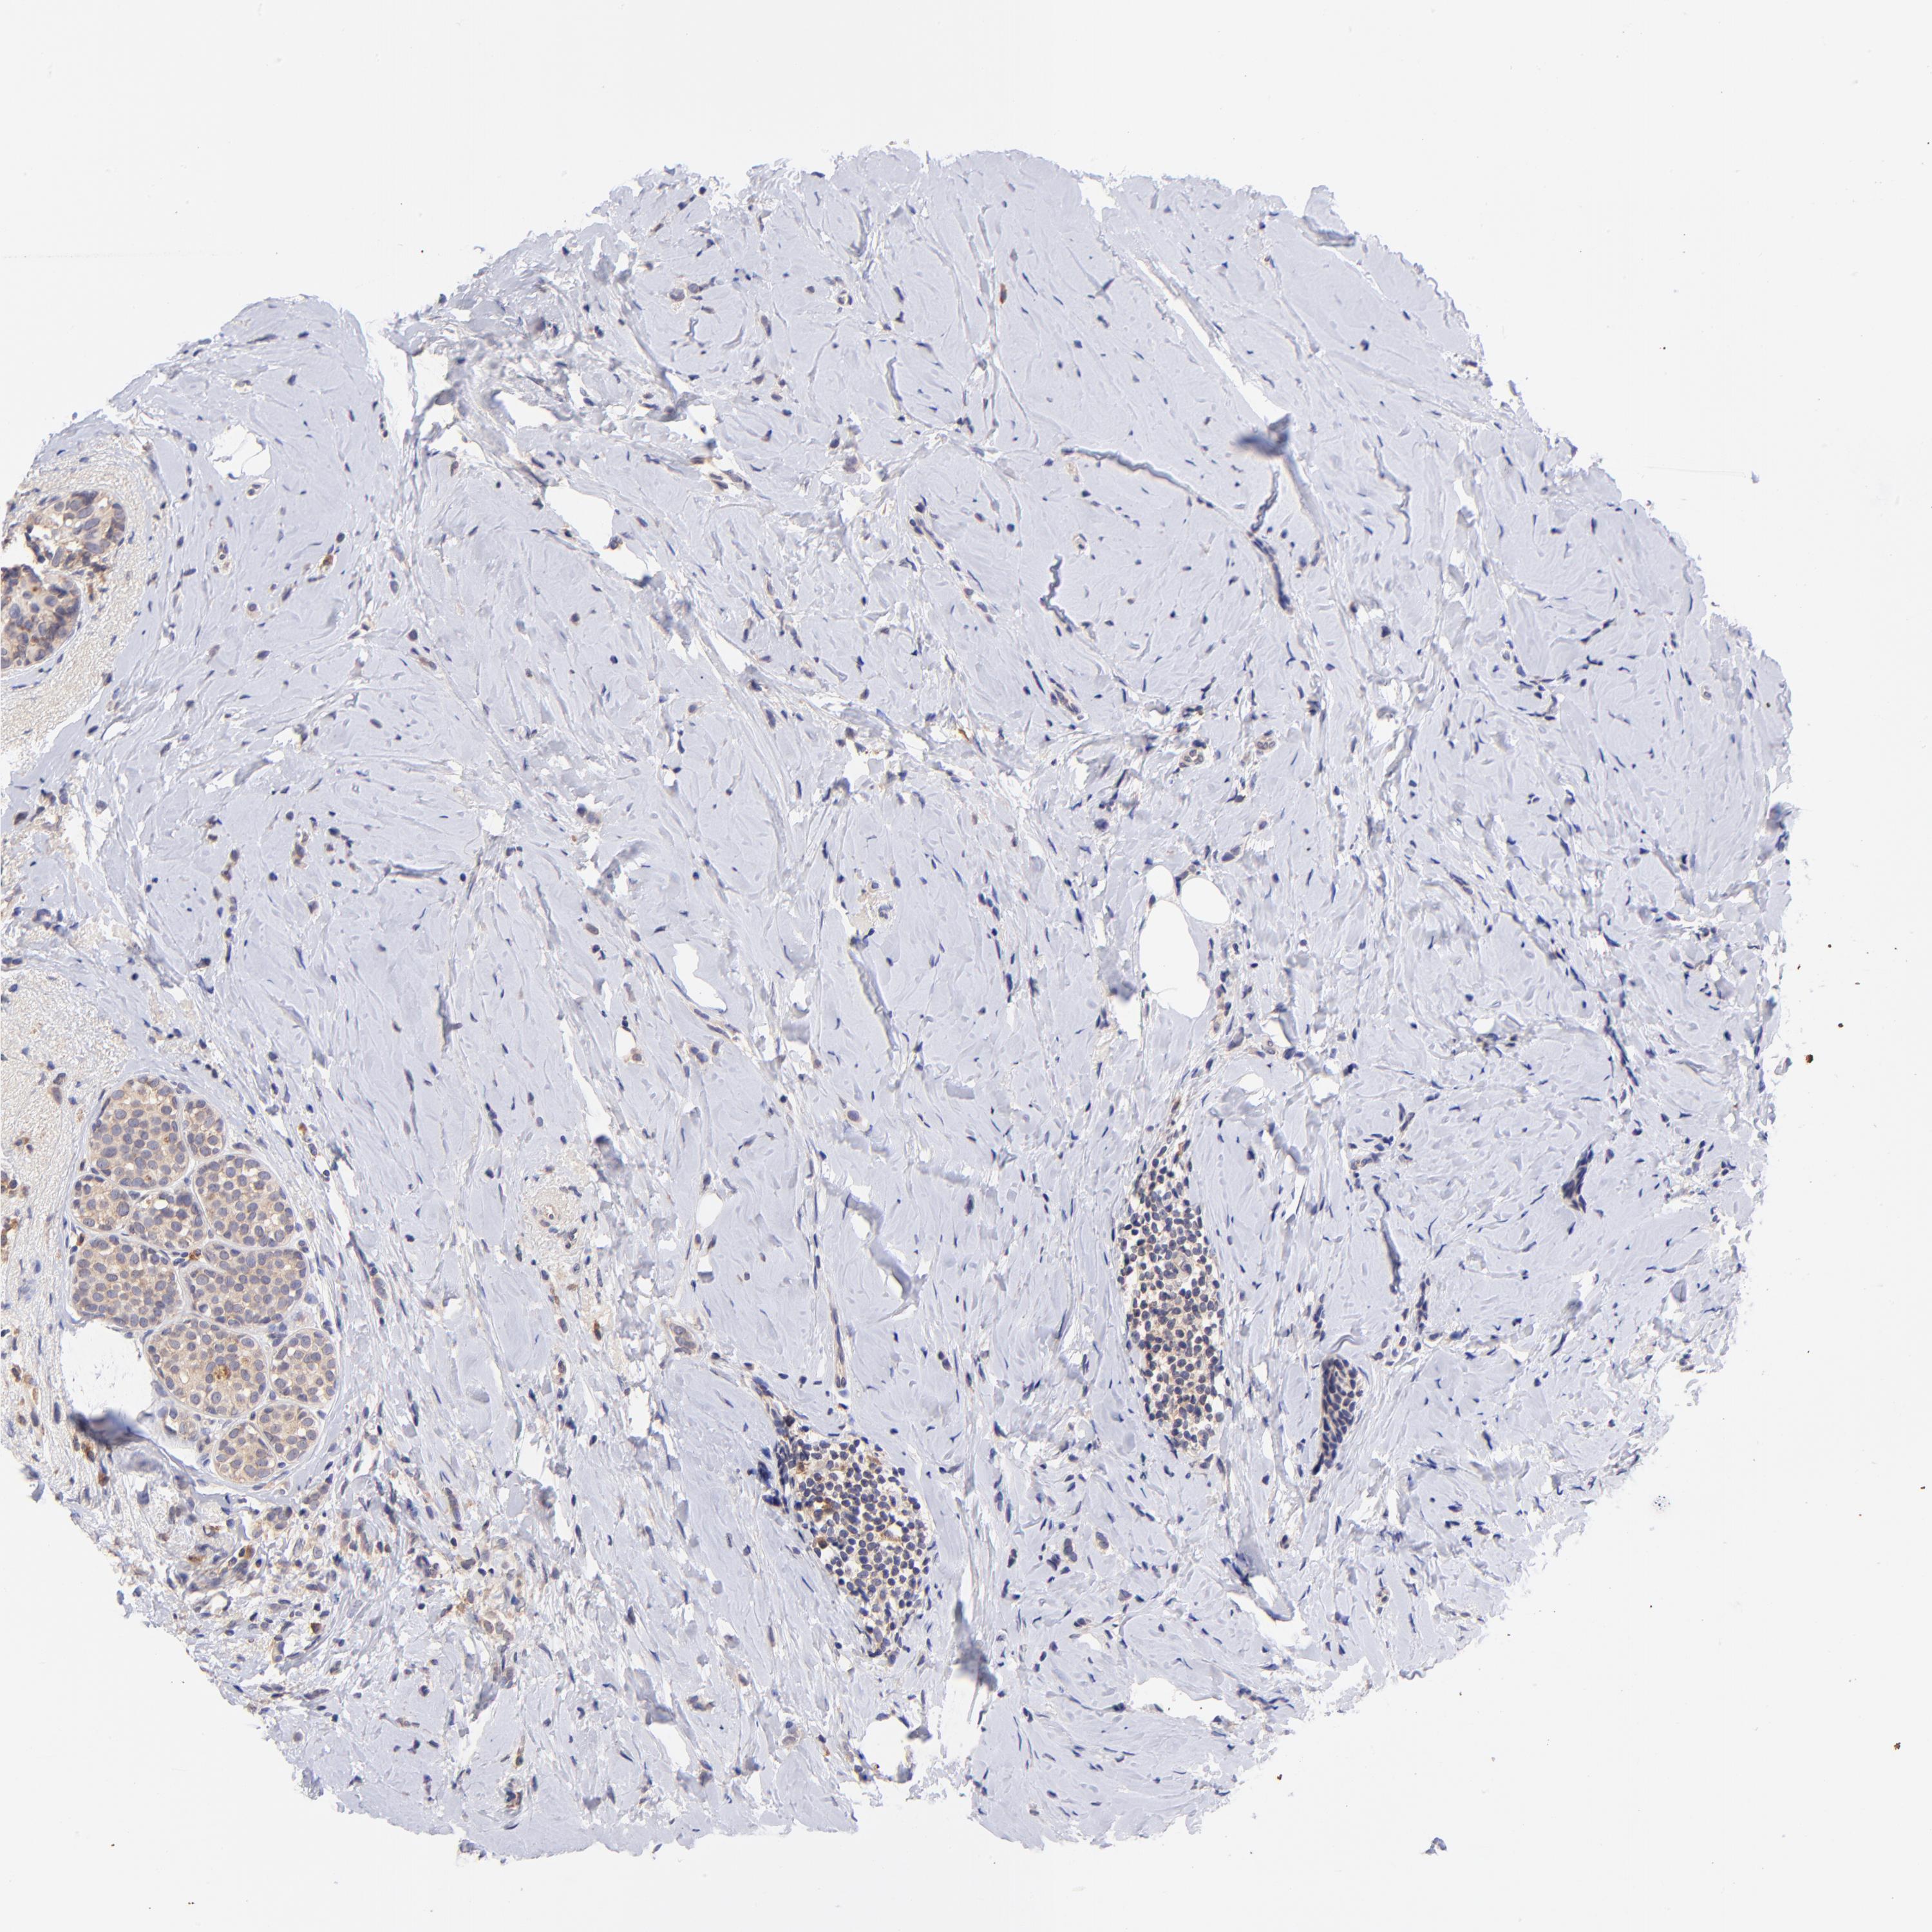

CANCER BREAST CANCER Show tissue menu

BRCA TCGA BRCA VALIDATION PROTEIN EXPRESSION

Breast cancer

Human cancer

RPL11 is not prognostic in Breast Invasive Carcinoma (TCGA)